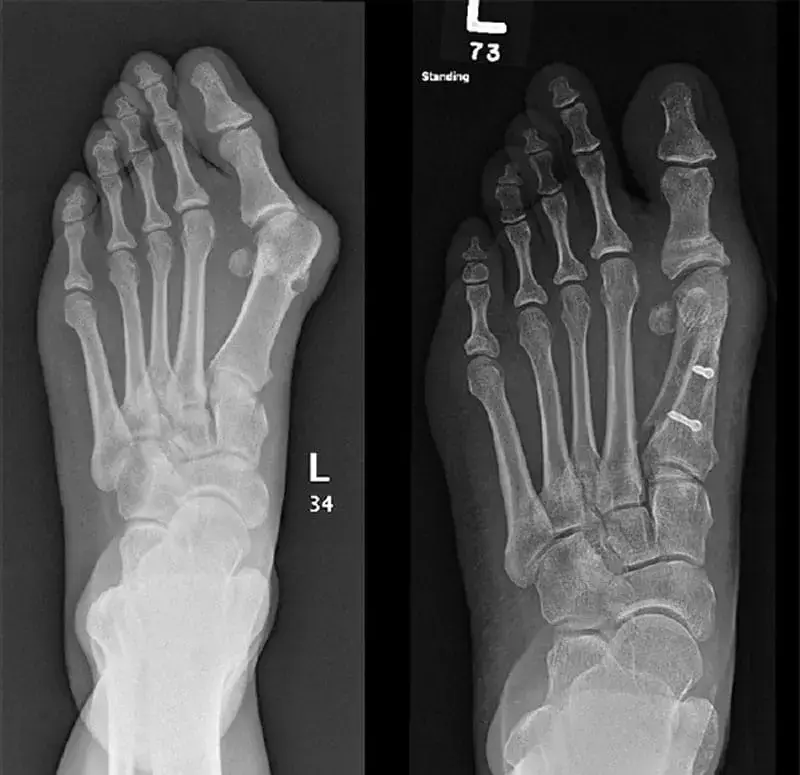

Zobacz, jak Maria wyleczyła koślawość w 7 dni:

Przez długi czas odczuwałam silny ból stóp. W rezultacie wystąpiły trudności w poruszaniu się. Poszłam do specjalisty i zdiagnozowano u mnie paluch koślawy. Zaproponowali mi operację stóp, ale za bardzo bałam się zabiegu. Na szczęście poznałam Andrzeja i zaczęłam używać Artisan. Po trzech dniach ból całkowicie ustąpił, a tydzień później chodziłem bez bólu i zaczęłam uprawiać nordic walking. Zdjęcie pokazuje moje postępy."